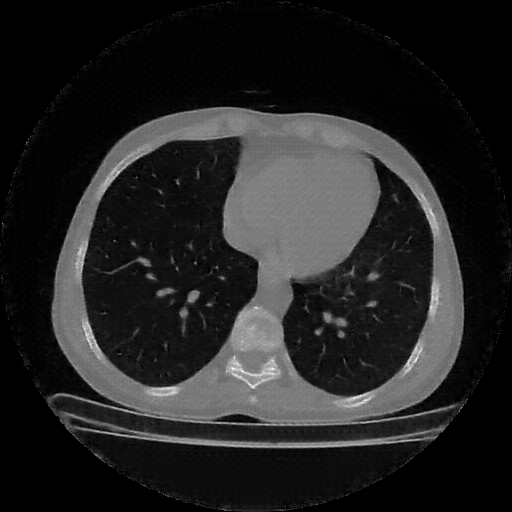

Generated VENOUS CT scan (A→B translation)

Full window (WL 1023.5, WW 4095 β†’ Low βˆ’1024, High +3071)

Lung window (WL -600, WW 1500 β†’ Low βˆ’1350, High +150)

Mediastinum window (WL 40, WW 400 β†’ Low βˆ’160, High +240)